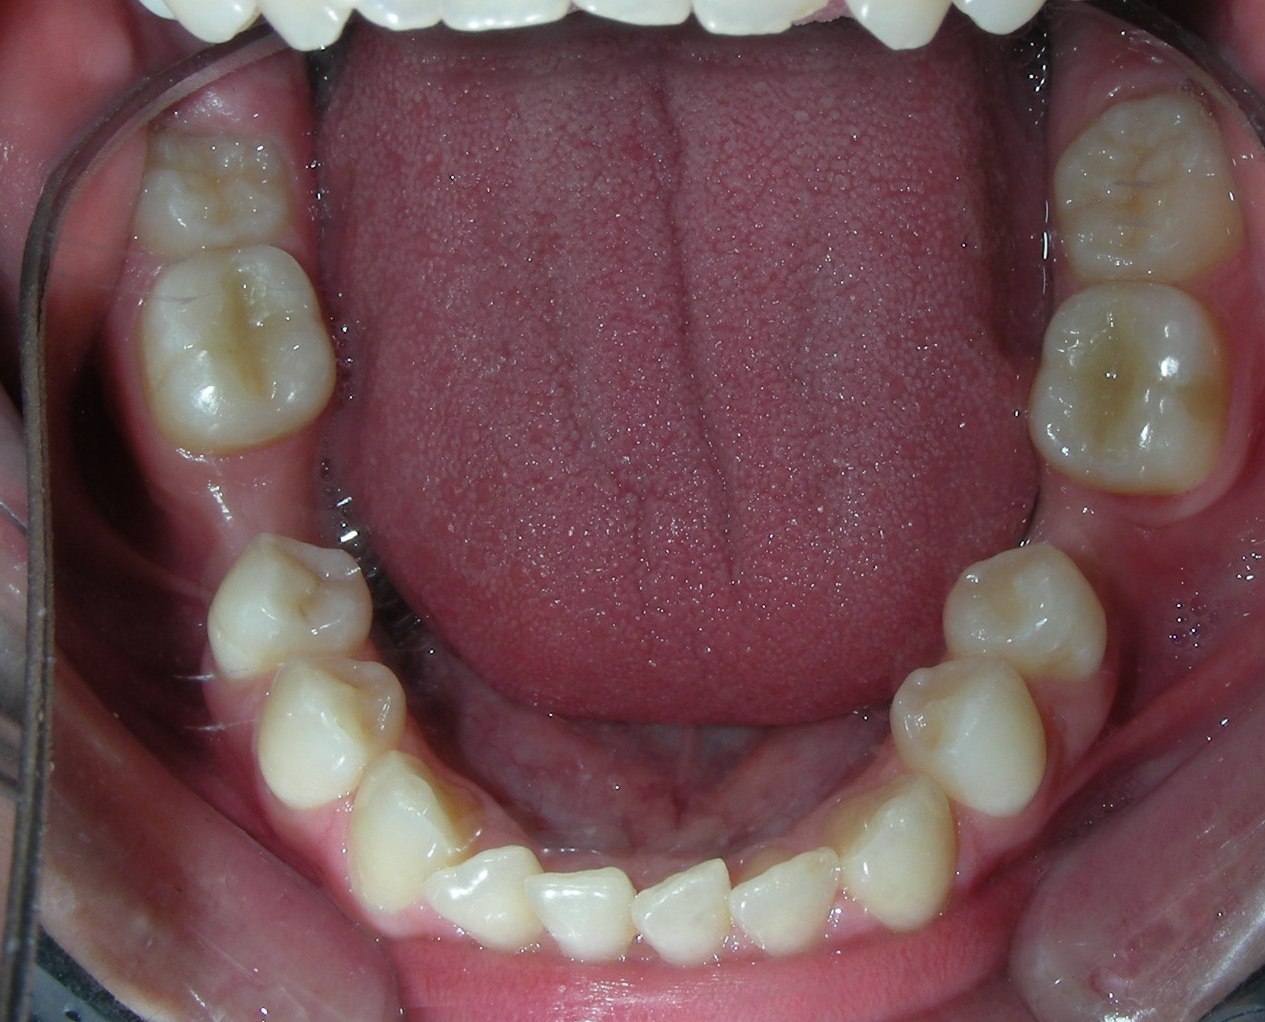

Simultaneously we begin with the alignment of the lower arch ,Simultaneously we began with the alignment of the lower arch with Roth prescription ceramic braces .022 . Henry Schein®

The upper brackets were bonded solely for the purpose of providing stability to the utility arch . Following the hierarchically structured treatment plan, we proceed with the alignment and leveling phase in order to enable mesialization of the posterior segments using sliding mechanics, which works effectively in conjunction with Roth prescription brackets .022.

A progressive archwire sequence was used for alignment, leveling, and three-dimensional control.

After two years of treatment using appropriate biomechanics, the overbite was successfully corrected from -8 mm to +1 mm, achieving complete closure of the anterior open bite without exacerbating the patient’s lower facial third vertical proportions. At this stage, occlusal contacts were verified using articulating paper, and functional movements of the canines and incisors were evaluated to ensure proper anterior guidance and disclusion patterns. The patient was then referred to speech therapy (myofunctional evaluation) as part of the pre-debond assessment protocol.